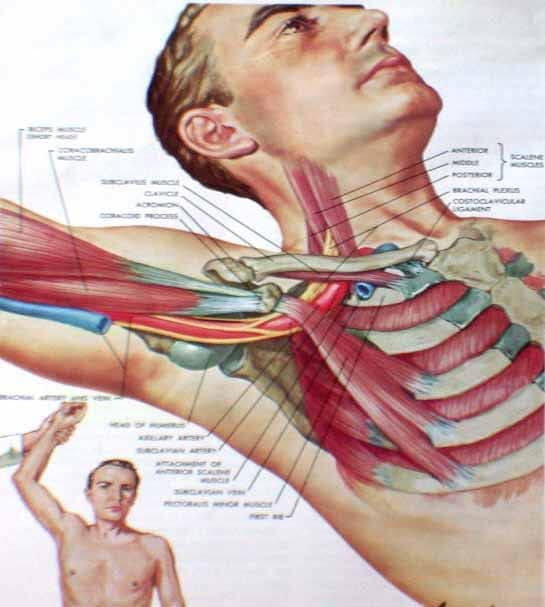

Hội chứng lối thoát ngực là một tình trạng, theo đó triệu chứng được tạo ra từ việc chèn ép các dây thần kinh, mạch máu, hoặc cả hai, vì một lối đi hẹp thông qua một khu vực (lối thoát ngực) giữa nền cổ và nách. Lối thoát ngực được bao quanh bởi cơ, xương và các mô khác. Bất kỳ tình trạng nào gây phì đại hay chuyển động của các mô hoặc gần lối thoát ngực đều có thể gây ra hội chứng lối thoát ngực. Các nguyên nhân thường gặp của hội chứng lối thoát ngực bao gồm chấn thương vật lý như một tai nạn xe hơi, tổn thương lặp đi lặp lại do công việc hoặc các hoạt động liên quan đến thể thao, một khuyết tật bẩm sinh nào đó (chẳng hạn như có một xương sườn phụ), mang thai, tăng cân, và các khối u ở phía trên của phổi (hiếm). Ngay cả một chấn thương dài trong quá khứ có thể dẫn đến hội chứng lối thoát ngực trong hiện tại. Đôi khi các bác sĩ không thể xác định nguyên nhân của hội chứng lối thoát ngực.

Hội chứng lối thoát ngực do căn nguyên thần kinh: loại này đặc trưng bởi sự chèn ép đám rồi thần kinh cánh tay. Đám rối thần kinh cánh tay là một mạng lưới các dây thần kinh xuất phát từ tuỷ sống, kiểm soát vận động của các cơ và cảm giác ở vai, cánh tay và bàn tay. Trong hầu hết trường hợp của hội chứng lối thoát ngực triệu chứng là về thần kinh.

Hội chứng lối thoát ngực do căn nguyên mạch máu: xảy ra khi một hoặc nhiều động mạch, tĩnh mạch dưới xương đòn bị chèn ép.

Nói chung, nguyên nhân của hội chứng lối thoát ngực là ép của các dây thần kinh và mạch máu trong lối thoát ngực, ngay dưới xương đòn. Nguyên nhân của sự chèn ép bao gồm :